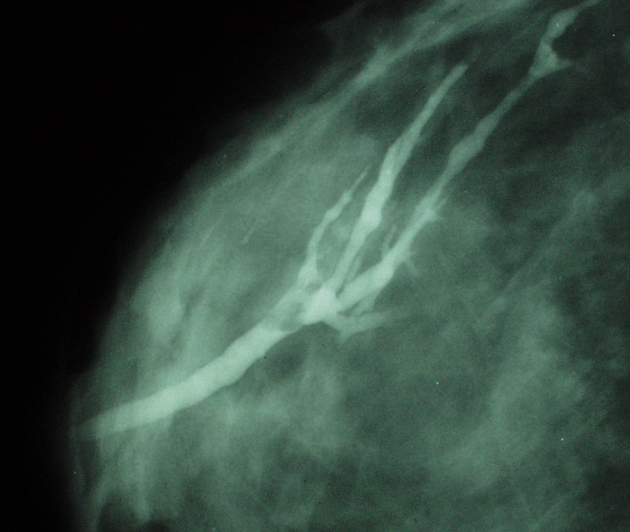

Diagnosis? Exam?

Intraductal papilloma.

Galactogram. Filling defect within a duct, described by location: central (70-90%) or peripheral.

Intraductal papilloma US appearance?

Differential?

Well-defined, smooth-walled, solid, hypo-echoic mass or a lobulated, smooth-walled, cystic lesion with some solid components. May see internal flow, vascular stalk. A dilated duct can be frequently visible sonographically.

Pappilary carcinoma- usually presents as an intracystic mass or mural nodules within a cystic mass. More likely to have an irregular shape.